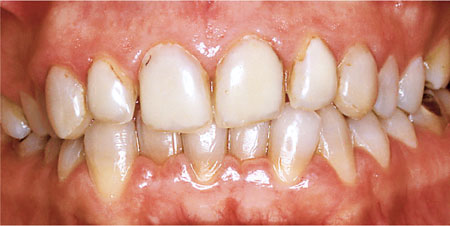

Indirect restorations should not be considered until the treatment in Table 1-2 has been carried out, reevaluated and found to be successful. There should be no signs of active periodontal disease in relation to the tooth being restored, such as bleeding on probing. Even gingival bleeding with a BPE score of 1 will make impression taking difficult and the resulting restoration is likely to have a poor fit. Consequently more plaque accumulation occurs and the disease process is perpetuated. Additionally, gingival inflammation at the time of placement will lead to bleeding and excess gingival crevicular fluid, which may compromise the cement lute. This predisposes to sensitivity, secondary caries and staining around tooth coloured restorations, including all-ceramic crowns and veneers (Fig 1-9).

Fig 1-9 Poor gingival health at the time of placement of these composite vaneers compromised bonding leading to microleakage and staining of the restoration margins.